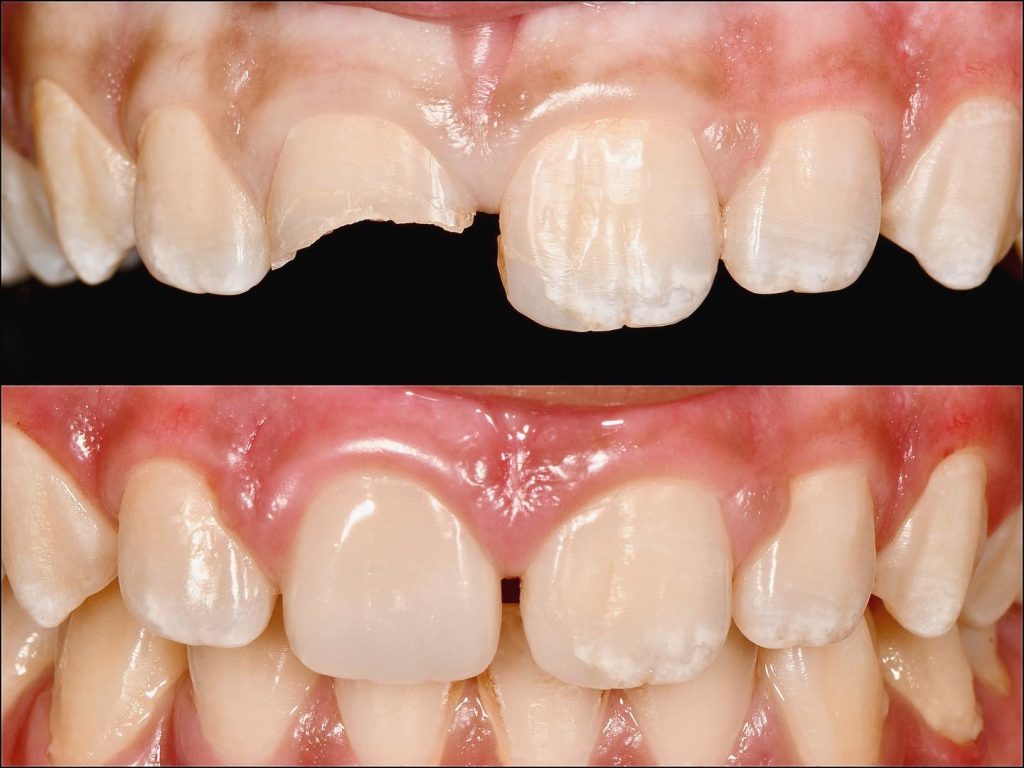

10 years old child, visited us with parents, he was fallen in school and traumatised in his upper central incisor.

there are no signs or symptoms, but looking for esthetic in his smile.

After examining the case, the tooth was vital and there no any changes in x ray .

so we treated this incisor with direct composite restoration.

follow up after 3 months